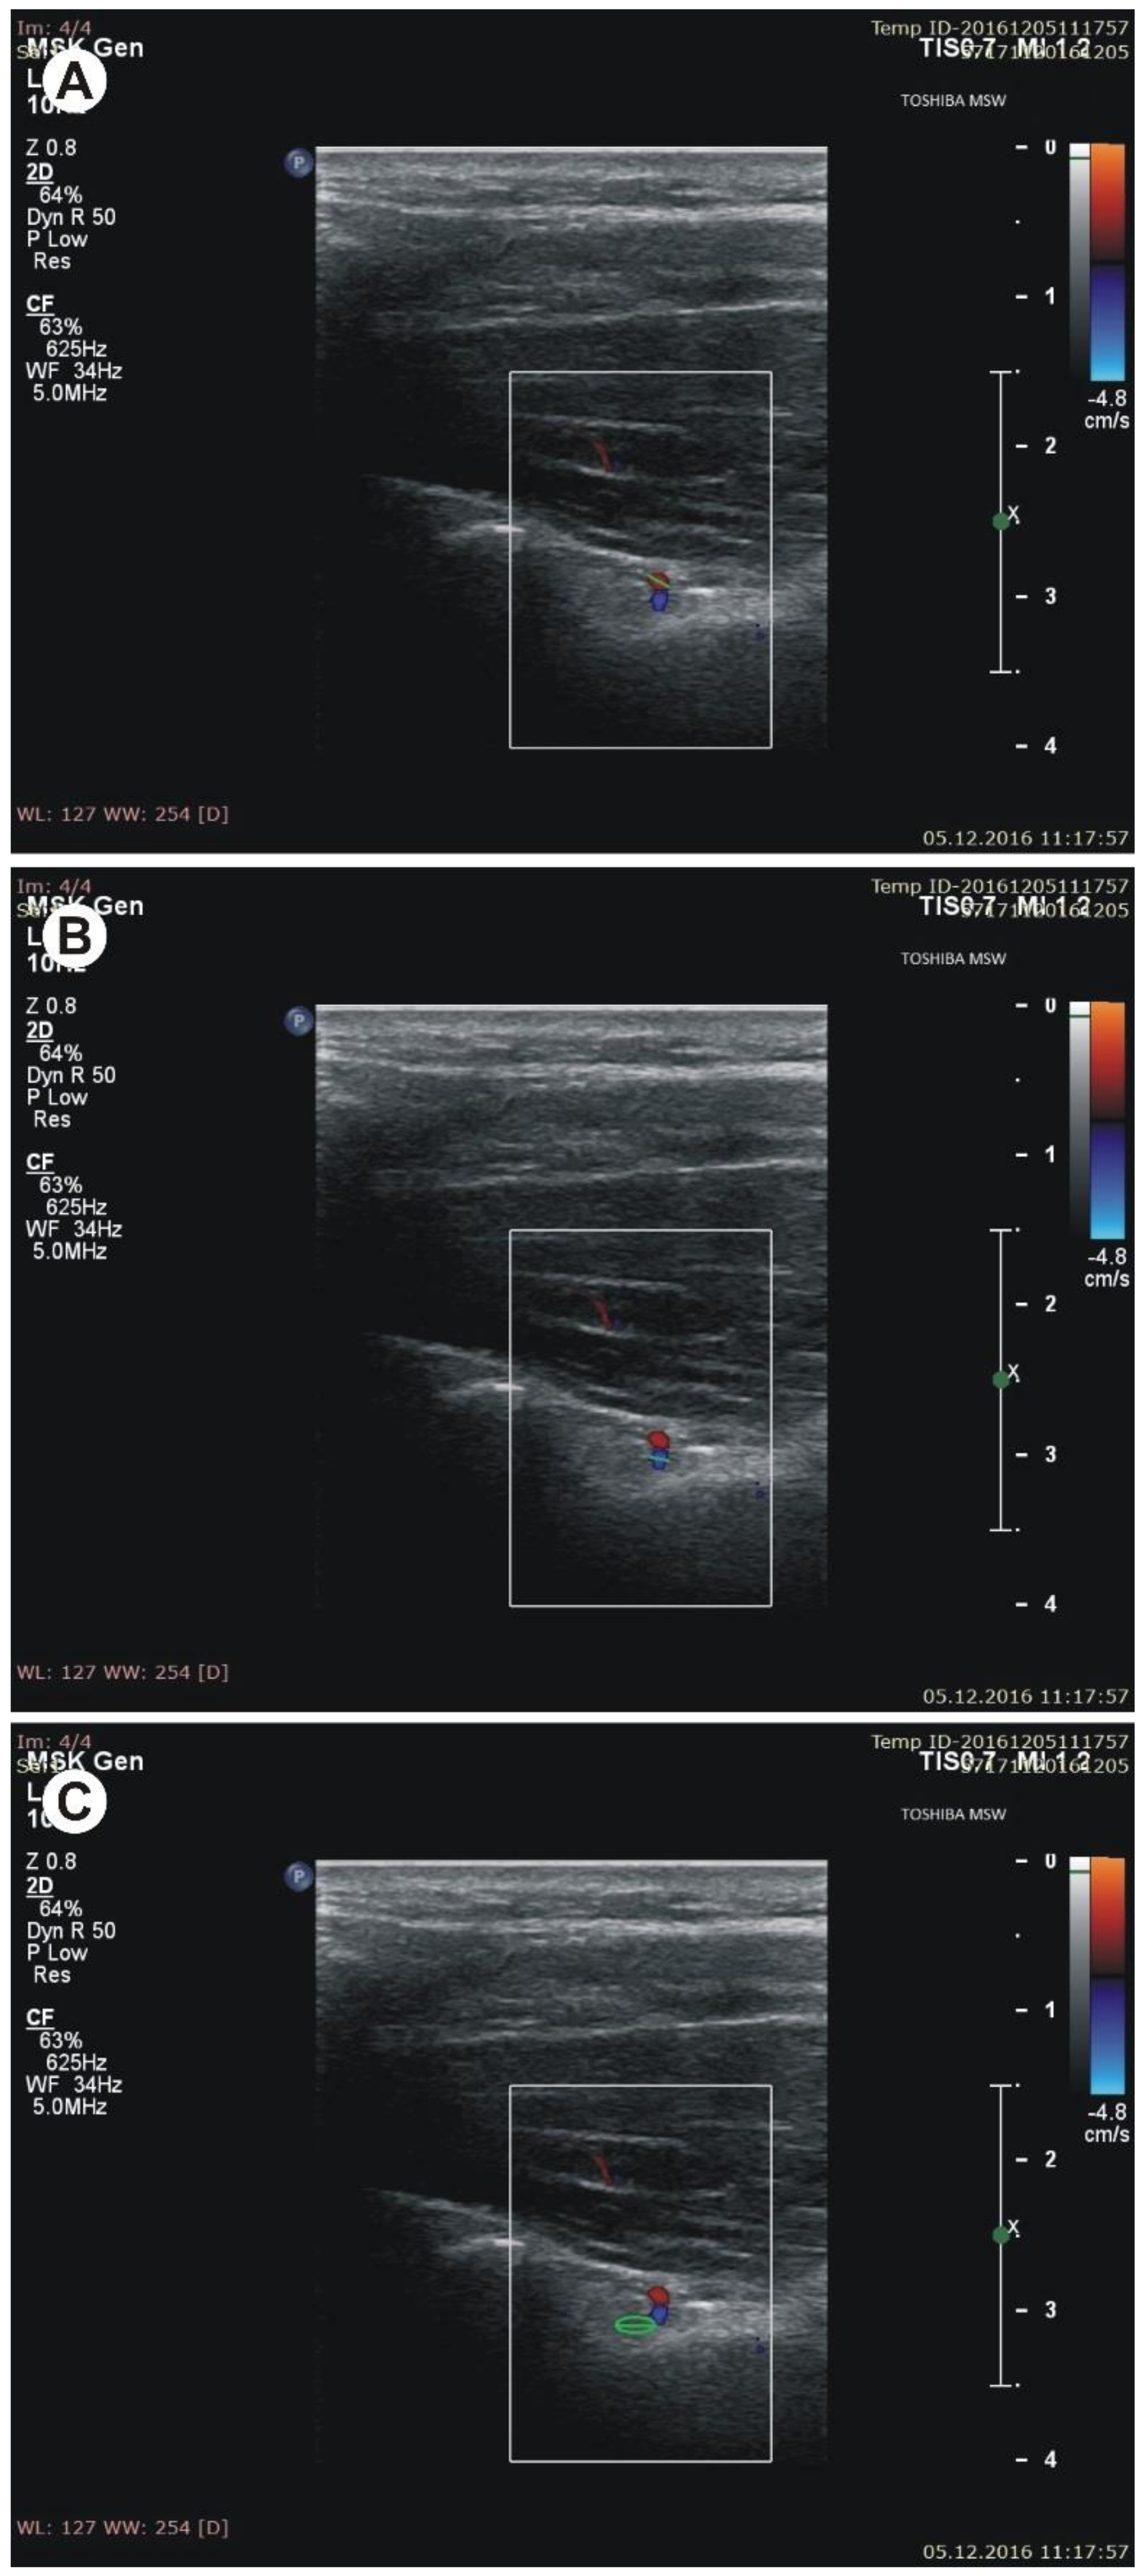

Figure 3. Measurements of structures at the suprascapular notch (SSN) notch region during sonographic examination. (A) diameter of the suprascapular artery; (B) diameter of the suprascapular vein; (C) diameter of the suprascapular nerve. - (d)

- the diameter of the suprascapular artery (Figure 3A)

- the diameter of the suprascapular vein (Figure 3B)

- the diameter of the suprascapular nerve (Figure 3C)